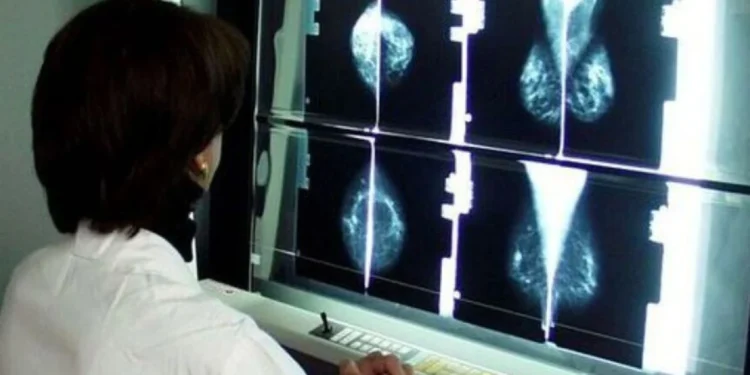

Por Alessandro Vittorio Romano — Um estudo da Hebrew University of Jerusalem, publicado em Cell Death & Disease, revela que o câncer de mama em mulheres portadoras de mutações BRCA1 e BRCA2 deixa marcas no genoma muito antes de qualquer lesão tumoral ser detectável. Essas marcas aparecem como rupturas de DNA em locais específicos — uma espécie de mapa de fragilidade que precede o tumor por anos.

Os pesquisadores analisaram células epiteliais mamárias aparentemente saudáveis, porém de alto risco, isoladas de mulheres portadoras das mutações. Ao traçar, pela primeira vez, um panorama completo das quebras de dupla hélice do DNA (DSB) nessas células, a equipe encontrou um padrão que não só difere profundamente do observado em células normais, como é surpreendentemente semelhante ao perfil encontrado em tumores mamários já estabelecidos.